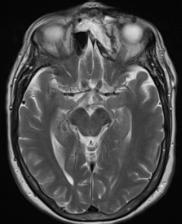

Sjúklingur er áberandi úteygð (exopthalmos) og með hliðartilfærslu á vinstra auga (mynd 1a). Við mat á heilataugum III, IV og VI kemur fram að sjúklingur á erfitt með að horfa upp og tvísýni versnar þegar hún horfir upp og til hægri. Lífsmörk eru innan viðmiðunarmarka og önnur líkamsskoðun ómarkverð.

a) MRI mynd af höfði sjúklings fyrir aðgerð. Vinstra auga er útstætt vegna fyrirferðar slímblöðrunnar.

b) Þrívíddarmódel af höfuðkúpu sjúklings. Hér má sjá hvernig slímblaðran er vaxin í augntótt.

Fyrir aðgerðina var hannað módel með þrívíddarprentara (mynd 1b). Teknar voru tölvusneiðmyndir og segulsneiðmyndir sem stuðst var við í tölvustýrðri myndleiðsögn meðan á aðgerðinni stóð. Til að tryggja þétta lokun milli ne ols og heila og tilfærslu æðaríks ve ar á svæðið var notaður frír flipi. Sjúklingur fékk fræðslu um fyrirhugaða aðgerð og hugsanlega fylgikvilla. Gerður var skurður frá eyra til eyra (bicoronal) og húðinni af enni flett fram, niður að augntótt og superior orbital taugin frílögð. Beinplata yfir ennisblaði og augntótt var söguð frá og heilahimna losuð til að bæta aðgengi. Bakveggur ennisholu var arlægður og öll slímhúð beggja vegna hreinsuð burt. Beinþakið á augntóttinni var sagað laust og losað frá. Beinið, sem var afmyndað, var þynnt með demantsbor, sárið skolað og öll slímhúð á svæðinu arlægð Í kjölfarið var augntóttin endurgerð með beingröftum. Skorinn var upp fremri lærisflipi (anterolateral thigh flap) samsettur úr vöðvafelli og litlum vöðvabita frá vastus lateralis og tengdur á sameiginlegum æðastilk frá circumflex femoralis æðinni (mynd 2). Flipinn var síðan staðsettur ofan við endurgerða augntóttina og vöðvabitinn lagður inn í ne olið. Í gegnum holu í ennisbeininu var æðastilkurinn frá flipanum þræddur út. Með aðstoð smásjár var gagnaugaæðin (temporal artery) saumuð saman með Ethylon 9.0 og bláæðin tengd með 2,5 mm hring áföstum doppler til að hægt væri að fylgjast með blóðflæði til og frá flipanum fyrstu dagana eftir aðgerð Beinplatan frá ennisblaði var síðan fest aftur með þunnum járnplötum og skrúfum, húðinni flett yfir svæðið, sinafell saumað og húð heftuð saman. Á mynd 3 má sjá sárið fyrir og eftir ígræðslu flipans. Aðgerðartími var um 6 klukkustundir.

Bataferlið gekk vel og sjúklingur losnaði við tvísýni og höfuðverkjaköst. Á mynd 4 sést hvernig úteygða og tilfærsla á vinstra auga gekk nánast alveg til baka. Líðan og lífsgæði sjúklings bötnuðu til muna.

a) MRI mynd af höfði sjúklings eftir aðgerð. Slímblaðran er horfin og augntótt komin í eðlilega stöðu.

b) Ljósmynd af augum sjúklings. Úteygða og tilfærsla á vinstra auga er gengin til baka.